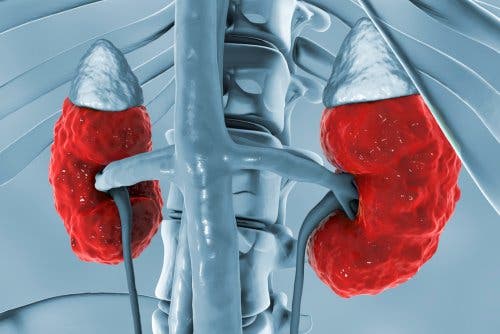

Effetti sui reni

Agisce sui reni per migliorare una serie di processi che concentrano l’urina. Promuovendo la concentrazione di urina, la vasopressina provoca il riassorbimento netto di acqua libera da parte del fluido extracellulare.

La vasopressina agisce sul rene dando luogo a tre effetti principali:

- Aumenta la permeabilità all’acqua dei tubuli collettori iniziali e corticali. Inoltre, incrementa quella del dotto midollare esterno e interno del rene. In questo modo, si verificano un riassorbimento di acqua e l’espulsione dell’urina maggiormente concentrata.

- Incrementa la permeabilità della porzione midollare interna del dotto collettore verso l’urea.

- Aumento dell’assorbimento di sodio attraverso l’ansa ascendente di Henle.